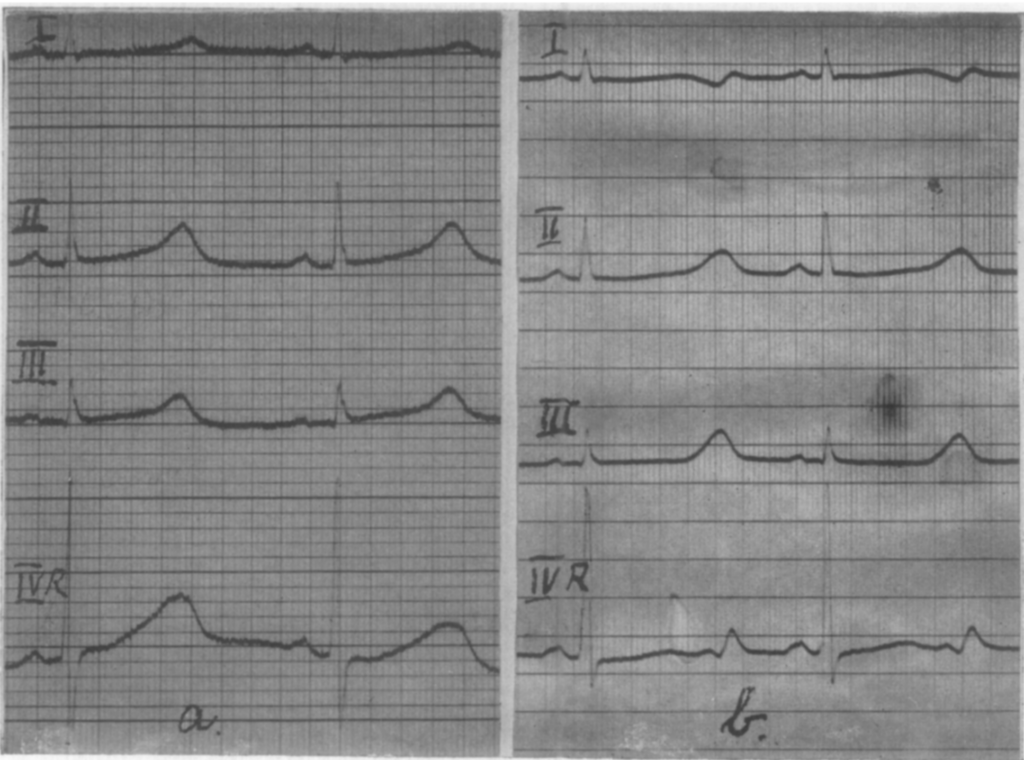

(a) ECG July 20. 1953, during rest. Leads I, II, III. IVR. Q-T = 0.50s. R-R = 0.88s.

(b) ECG July 20, 1953. after stair-running. Leads I. II. III, IVR. Q-T = 0.60s R-R = 0.86s. Jervell A, Lange-Nielsen F. 1957